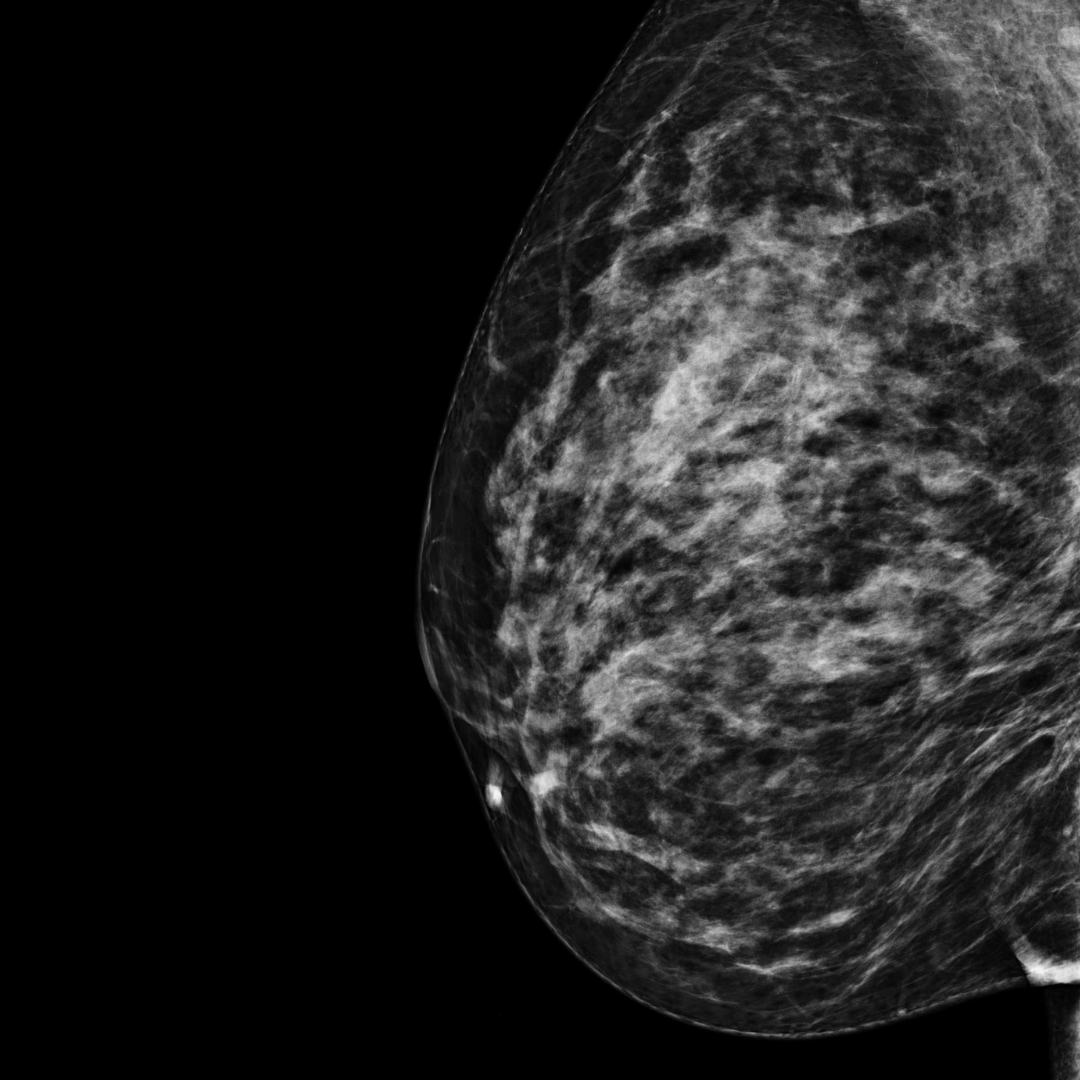

Category C

BI-RADS category C:

The breasts are heterogeneously dense. The breast tissue is dense.